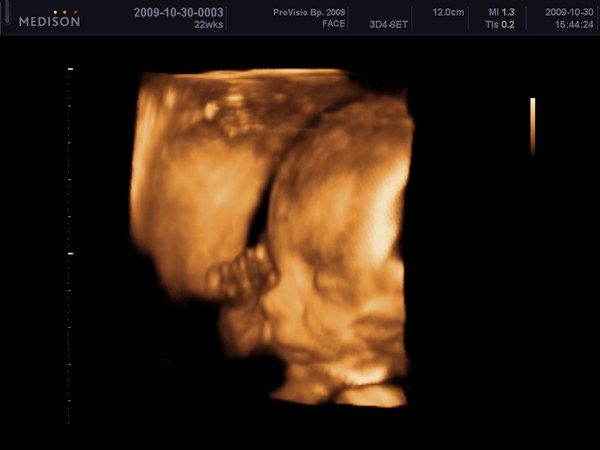

Katica, szuper lehetett ez a vizsgálat, de a legnagyszerűbb, hogy mindent rendben találtak.

Tegnap 3/4 3-tól majdnem 5-ig vártam a dokira, hogy megnézzük Botondot, és, hogy nem okozott-e valami bajt a hételeji tányérbecsapódás a hasamba. A lényeg: nem látszott semmi baj, Botondka is szépen növöget, és képzeljétek a "rohamos súlygyarapodásra" -mert így írta be a kiskönyvembe a védőnő, azt mondta a doki, hogy ne foglalkozzak vele, és viccesen hozzáfűzte: jó, hogy nem szereltetünk be egy futópadot ide a vizsgálóba, hogy aztán még büntessük is a kismamákat, amiért hízni mertek.